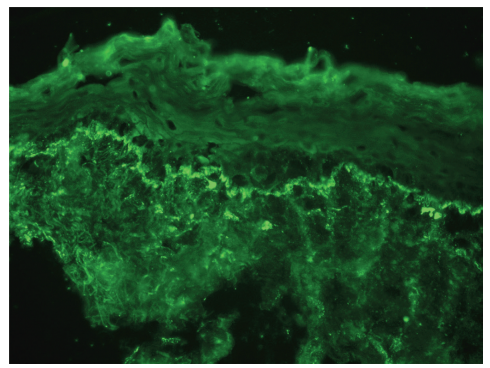

Lesional Biopsy:

Histopathology: Shows mild interface dermatitis with vacuolization of basal keratinocytes and sparse superficial lymphoid infiltrates.

Direct immunofluorescence may reveal granular deposits of IgG and/or IgM in lesions.